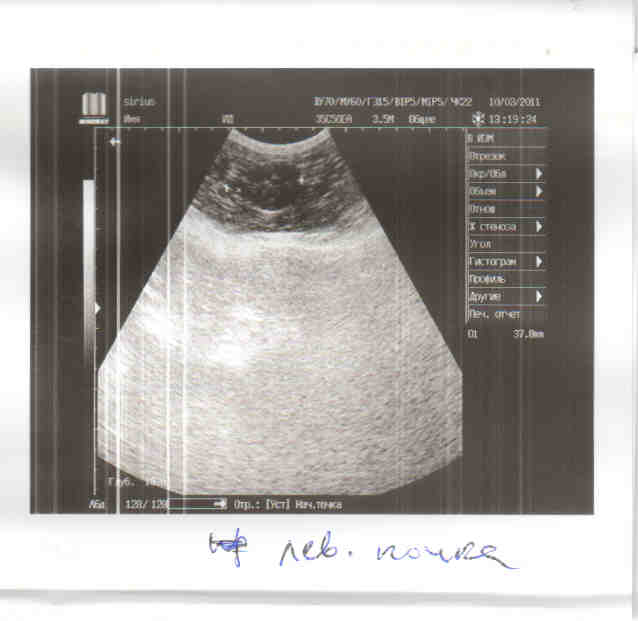

Мне нужна финансовая помощь, конечно большая часть с меня, но все я не потяну сразу. Выкладываю лист назначений, еще не посчитан стационар, т.к. неизвестно как пройдет операция. По состоянию кошка в норме, температура нормальная, почки в норме, а вот с печень небольшие проблемы, нужно будет ее поддержать.